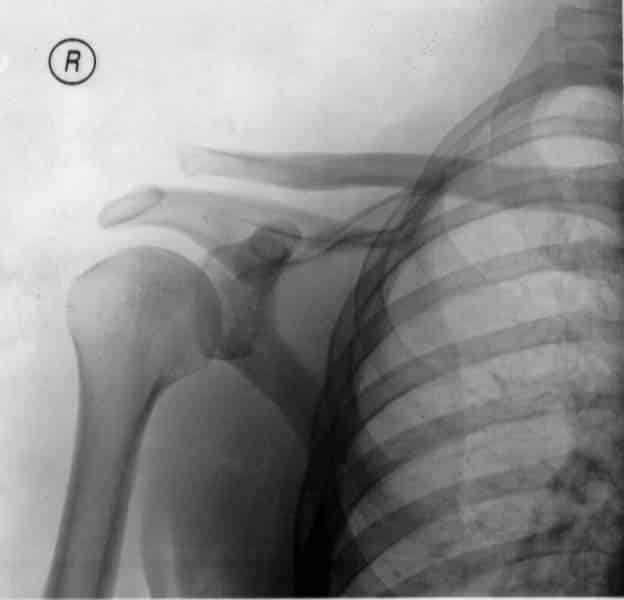

The acromioclavicular joint is an articulation in the shoulder region between the clavicle and the acromion of the scapula. It is a plane type synovial joint. In this article, we shall look at the anatomy of the acromioclavicular joint – its anatomical structure, neurovascular supply and any clinical correlations. By TeachMeSeries Ltd (2025) Fig 1Articulating surfaces of the acromioclavicular joint. Pro Feature - 3D Model You've Discovered a Pro Feature Access our 3D Model Library Explore, cut, dissect, annotate and manipulate our 3D models to visualise anatomy in a dynamic, interactive way. Learn More Anatomical Structure Articulating Surfaces The acromioclavicular joint consists of an articulation between the lateral end of the clavicle and the acromion of the scapula. It has two atypical features: Articular surfaces of the joint are lined with fibrocartilage – as opposed to hyaline cartilage. Joint cavity is partially divided by an articular disc – a wedge of fibrocartilage suspended from the upper part of the capsule. Joint Capsule The joint capsule of the acromioclavicular joint encloses the two articular surfaces. It consists of a loose layer of fibrous tissue, which is lined internally by a synovial membrane. The posterior aspect of the joint capsule is reinforced by fibres from the trapezius muscle. Ligaments There are three main ligaments that strengthen and stabilise the acromioclavicular joint: Acromioclavicular ligament – runs horizontally from the acromion to the lateral clavicle. It covers the joint capsule, reinforcing its superior aspect. Conoid ligament – runs vertically from the coracoid process of the scapula to the conoid tubercle of the clavicle. Trapezoid ligament – runs from the coracoid process of the scapula to the trapezoid line of the clavicle. The conoid and trapezoid ligaments are collectively known as the coracoclavicular ligament. It is a very strong structure, effectively suspending the weight of the upper limb from the clavicle. By TeachMeSeries Ltd (2025) Fig 2The major ligaments of the acromioclavicular joint. Movements The acromioclavicular joint allows a gliding movement in the superior/inferior and anteroposterior planes, along with a small amount of axial rotation. As no muscle acts directly on the joint, all movements are passive, and are initiated by movement at other joints Blood Supply The arterial supply to the acromioclavicular joint is via the: Suprascapular artery – arises from the subclavian artery at the thyrocervical trunk. Thoracoacromial artery – arises from the axillary artery. The venous drainage accompanies the major arteries. Innervation The acromioclavicular joint is innervated by articular branches of the suprascapular and lateral pectoral nerves. They both arise directly from the brachial plexus. Clinical Relevance Acromioclavicular Dislocation Acromioclavicular joint dislocation (also known as a separated shoulder) occurs when the two articulating surfaces of the joint are separated. It most commonly occurs from a direct blow to the joint, or a fall on an outstretched hand. The injury is more serious if ligamental rupture occurs (acromioclavicular or coracoclavicular). If the coracoclavicular ligament is torn, the weight of the upper limb is not supported, and the shoulder drops inferiorly. Management of AC joint dislocation is dependent on injury severity and impact on quality of life. The treatment options range from ice and rest, to ligament reconstruction surgery. Note: this injury is not to be confused with shoulder dislocation – an injury affecting the glenohumeral joint. By Jay F. Cox (2006) [CC-BY-2.5], via Wikimedia Commons Fig 3Acromioclavicular joint dislocation Do you think you’re ready? Take the quiz below Pro Feature - Quiz The Acromioclavicular Joint Question 1 of 3 Submitting... Skip Next Rate question: You scored 0% Skipped: 0/3 1800 More Questions Available Upgrade to TeachMeAnatomy Pro Challenge yourself with over 1800 multiple-choice questions to reinforce learning Learn More Rate This Article